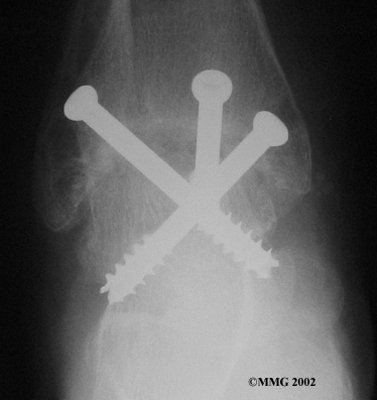

It is important when the surfaces are removed that the angles of the cut surfaces are correct. When the tibia is brought against the talus, the foot should be at a right angle to the lower leg. Once the cuts are made the bones must be held in place while they fuse. This can be done using large metal screws and metal plates if necessary. The screws are usually under the skin and are not removed unless they begin to rub and cause pain.

Inserting the screws

After ankle fusion, the physical therapists at FYZICAL North Cotner can help you learn to walk smoothly and without a limp. Although time needed for recovery varies among patients, an ankle brace will typically replace your cast after eight to 12 weeks. Your surgeon will take X-rays frequently to see if the bones are fusing together. You will probably need to use  crutches during the time you wear the cast. As the fusion grows stronger, you will begin to put more weight on your foot when walking.